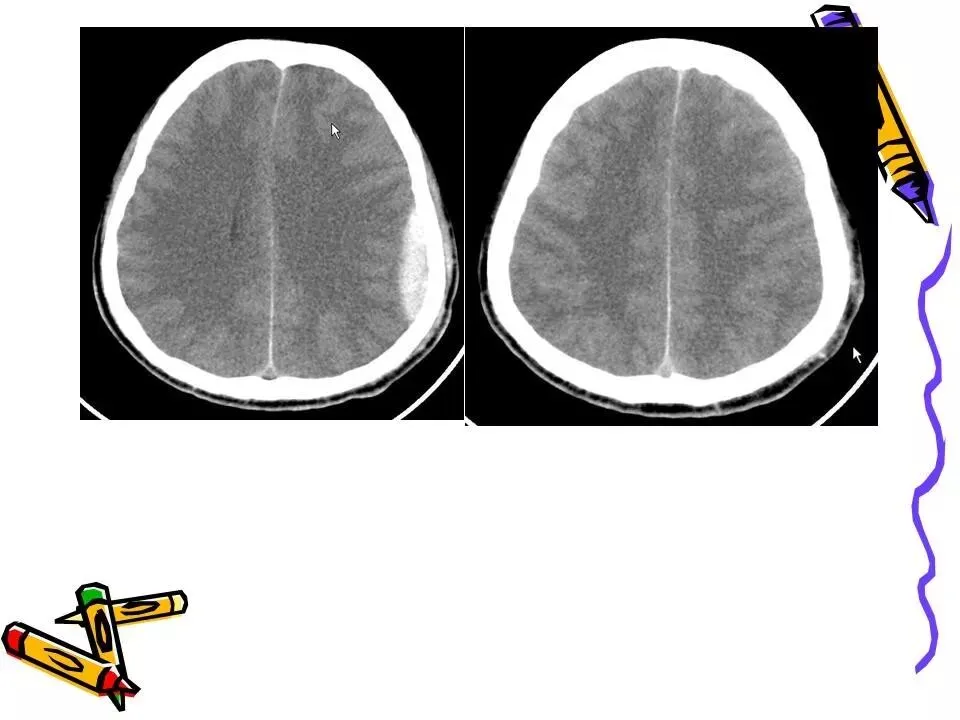

>常见颅脑外伤CT诊断(PPT)

常见颅脑外伤CT诊断(PPT)